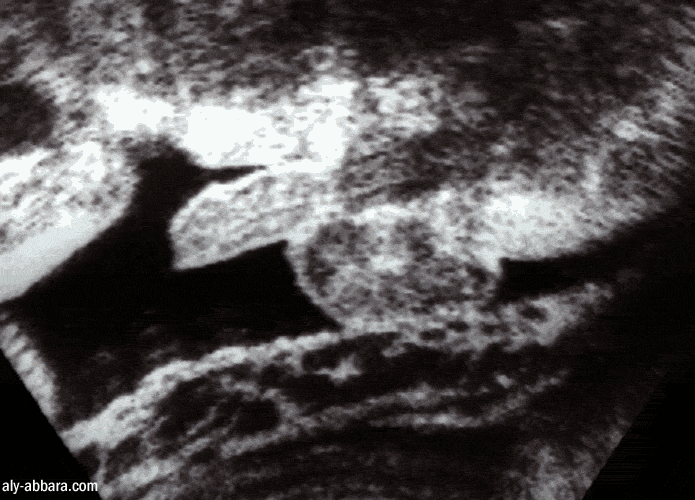

Organes génitaux externes masculins chez

un fœtus de 36 SA

Cette image met en évidence le trajet de l'urètre dans le pénis